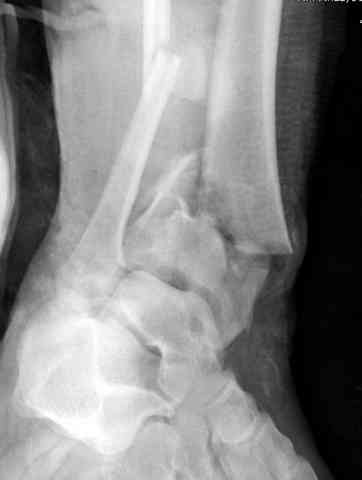

При лечении внутрисуставных переломов типа "Pilon"

или "Tibial Plateau" на голени, применение простых

наружных фиксаторов типа "Spanning ExFix" или "Travelling ExFix" стал одним из стандартом этапного лечения.

Дополнительные ренгенограммы после дистракции и

обязательная комьютерная томография дают возможности разузнать топографию расположения фрагментов, что немаловажно для планирования хирургического доступа.

По апексу фрагмента ориентируется при планировании

фиксации, также предоперационно определяется

направление фиксирующего материала: шурупа или спицы с упорной площадкой.

Здесь выставлена пара случаев перелома пилона, оба

случая леченные этапным наружным фиксатором.